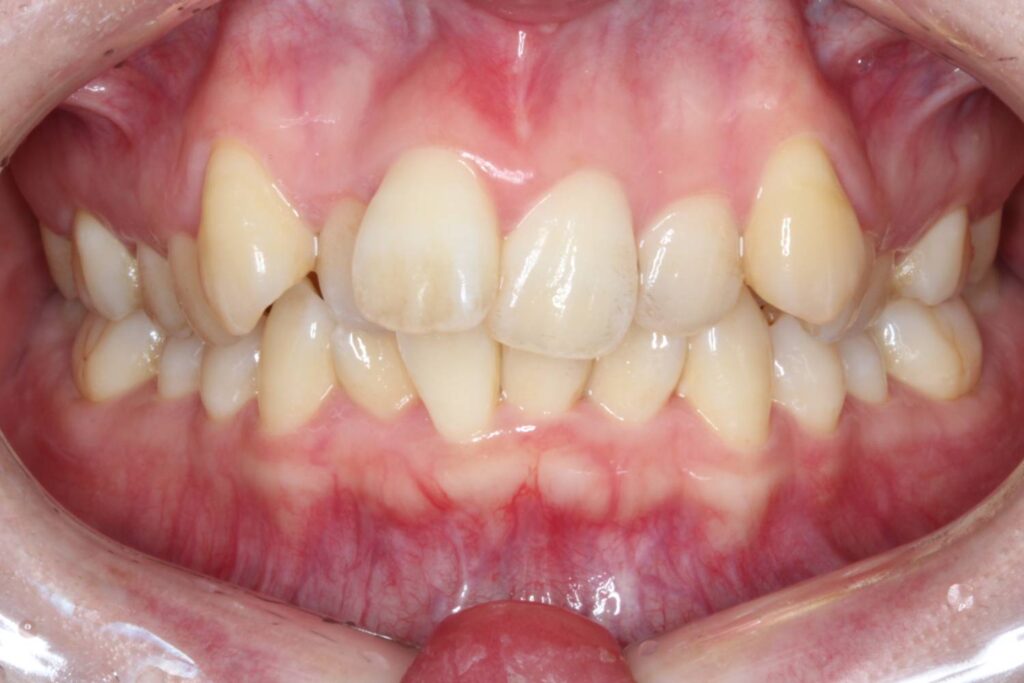

前歯に叢生があり、特に右上の前歯は前方に突出していて目立ってしまっています。

また、上顎の犬歯は「八重歯」と呼ばれる状態で、唇をよく噛んでしまったり、口内炎ができてしまうとのことでした。

奥歯の噛み合わせは、下顎に対して上顎が前方にずれてしまっています。

Before